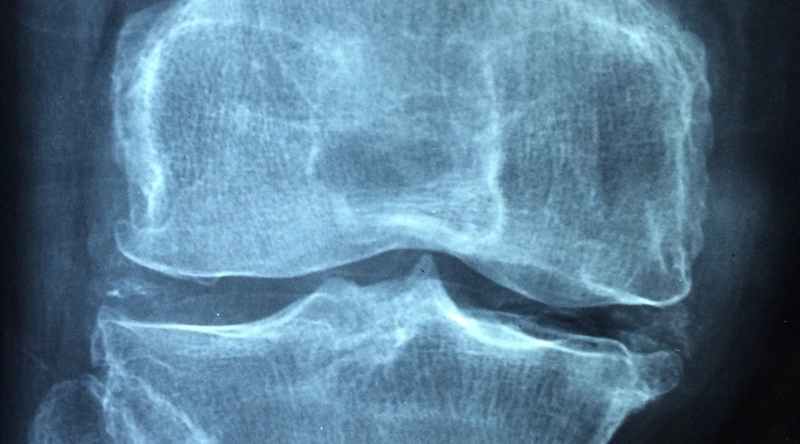

관절 건강은 단순히 통증을 관리하는 것을 넘어, 관절의 구조와 기능을 이해하고 이를 어떻게 보호할 수 있을지를 고민하는 과정입니다. 관절은 우리 몸에서 매우 복잡한 구조로, 뼈, 연골, 인대 등 여러 요소가 결합되어 있습니다. 이들 요소는 시간이 흐르면서 자연스럽게 노화되고, 사용 빈도가 높아질수록 더욱 손상될 수 있습니다. 특히, 무릎 관절은 체중을 지탱하는 역할을 하며, 그로 인해 타격을 많이 받는 부위입니다.

관절 건강을 지키기 위해서는 우선 관절의 주요 기능과 구조에 대해 이해하고, 이를 보호하기 위한 노력이 필요합니다. 관절이 아프거나 불편할 때는 곧바로 의사의 진료를 받고, 필요한 경우 물리치료나 다른 치료 방법을 고려해야 합니다. 이 과정은 예방의 첫걸음이 될 것이며, 초기 증상이 나타날 때 즉시 대처하는 것이 중요합니다.